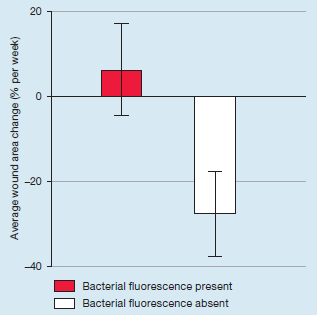

Integrating Point-of-Care Bacterial Fluorescence Imaging-Guided Care with Continued Wound Measurement for Enhanced Wound Area Reduction Monitoring

Derwin, R. et al. Diagnostics 2024

Integrating Point-of-Care Bacterial Fluorescence Imaging-Guided Care with Continued Wound Measurement for Enhanced Wound Area Reduction Monitoring

Derwin, R. et al. Diagnostics 2024